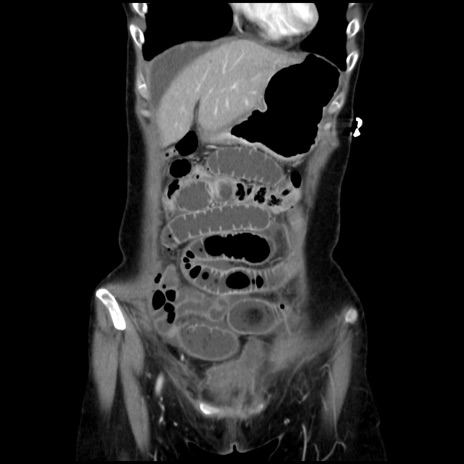

横断像